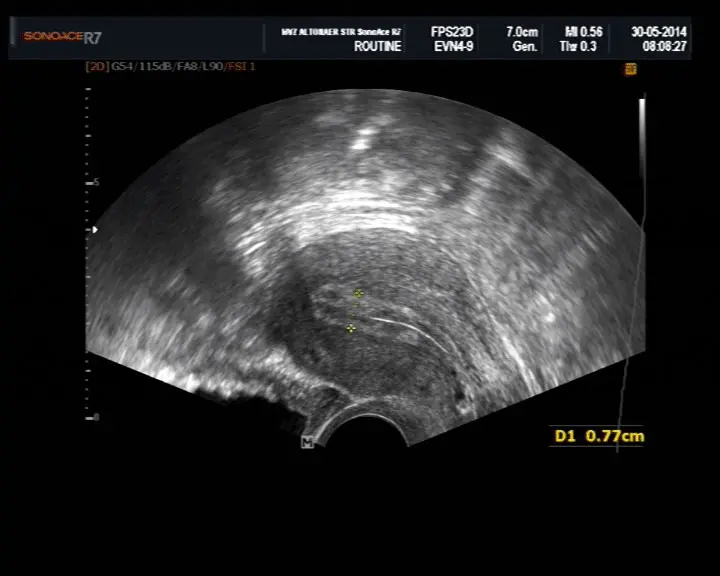

Der Ultraschall der Gebärmutterschleimhaut kann bereits in der frühen Schwangerschaft durchgeführt werden, um die Einnistung der Eizelle zu überprüfen. Die Untersuchung wird meist zwischen der und Schwangerschaftswoche durchgeführt. Der Ultraschall zeigt die Dicke und Struktur der Gebärmutterschleimhaut und kann auch die Einnistung der Eizelle sichtbar machen.

Die Dicke der Gebärmutterschleimhaut ist ein wichtiger Indikator für die Einnistung der Eizelle. Eine Dicke von 7 bis 8 mm gilt als optimal. Eine zu dünne Schleimhaut kann die Einnistung erschweren. Eine zu dicke Schleimhaut kann hingegen ein Zeichen für eine hormonelle Störung sein.

- Dicke der Gebärmutterschleimhaut: Die Dicke der Schleimhaut ist ein wichtiger Indikator für die Einnistung der Eizelle. Eine Dicke von 7 bis 8 mm gilt als optimal.

- Einnistung der Eizelle: Der Ultraschall kann die Einnistung der Eizelle in der Gebärmutterschleimhaut sichtbar machen.

- Fruchthöhle: Ab der Schwangerschaftswoche ist die Fruchthöhle im Ultraschall sichtbar.